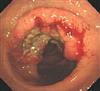

内視鏡所見は瀰漫性の糜燗、粘液付着、浮腫、出血が認められ、自然と正常粘膜への移行が見られるのが特徴です(中図)。 まれにスキップ(飛び火)して回盲部(虫垂のみの場合もある)に同性状のびまん性糜燗がみられることがあります(下図)。

何らかの原因により大腸の粘膜に炎症が起こり、びらん(ただれ)や浅い潰瘍ができる病気で、難病に指定され、最近急増し(上図)、なにかと話題である「炎症性腸疾患」です。

下痢や粘血便(血液・粘液の混じった軟便)、テネスムス、貧血、微熱や体重減 少などの症状があらわれます。 炎症は通常、肛門に近い直腸から始まり口側 の深部結腸に向かって炎症が進展していきます。 最深部の盲腸までの全大 腸に炎症が及ぶこともあります。 適切な治療により、進展とは逆に深部の結 腸から直腸に向けてびらん・潰瘍が修復されてきます。